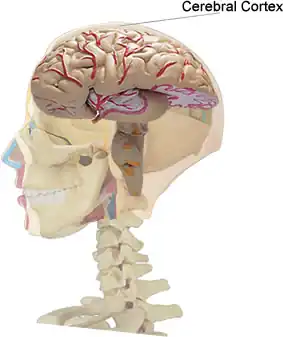

Cortex cérébral

Le cortex cérébral (ou écorce cérébrale[1]), d'origine prosencéphalique, est la substance grise périphérique des hémisphères cérébraux. Il se compose de trois couches (pour l'archi- et le paléocortex) à six couches (pour le néocortex) renfermant différentes classes de neurones, d'interneurones et de cellules gliales. Le cortex peut être segmenté en différentes aires selon des critères cytoarchitectoniques (nombre de couches, type de neurones), de leur connexions, notamment avec le thalamus, et de leur fonction. On pense que l'existence de ces circuits serait à l'origine de la pensée.

Anatomie

Chez l'être humain, l'épaisseur du cortex est comprise entre 1 et 4,5 millimètres[13] et sa surface avoisine 2 600 centimètres carrés (0,26 m2)[12], soit une surface dix fois plus importante que le singe[14]. Il contient environ 16[15] des 86 (voire 100[16]) milliards de neurones qui composent le cerveau humain.

Afin de pouvoir loger dans la boîte crânienne, le cortex est plissé par des sillons (sulcus en latin scientifique) ou scissures, de profondeur variable, délimitant des crêtes appelées gyrus[17] ou circonvolutions cérébrales.